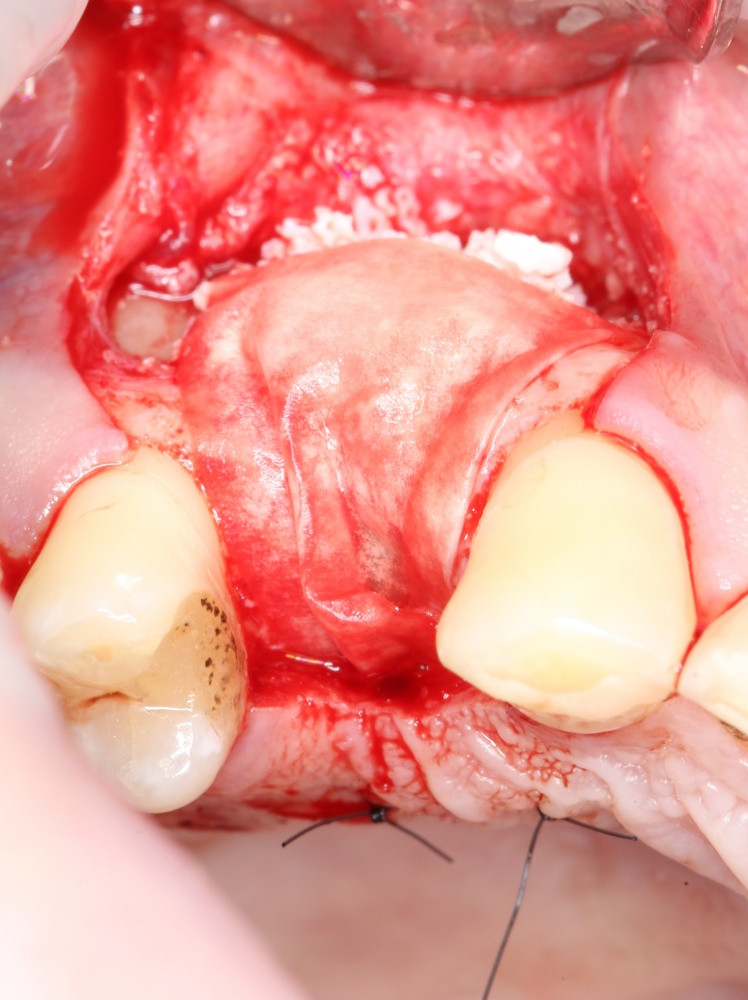

Далее, можем приступить к установке имплантатов. Разумеется. по хирургическому шаблону:

Последняя картинка даёт представление о том, какой объем костной ткани мы «нарастили».

Поскольку принимающее ложе и аутокостный блок конгруэнтны, мы можем отказаться от использования барьерной мембраны. Она не нужна.

Осталось только наложить швы: